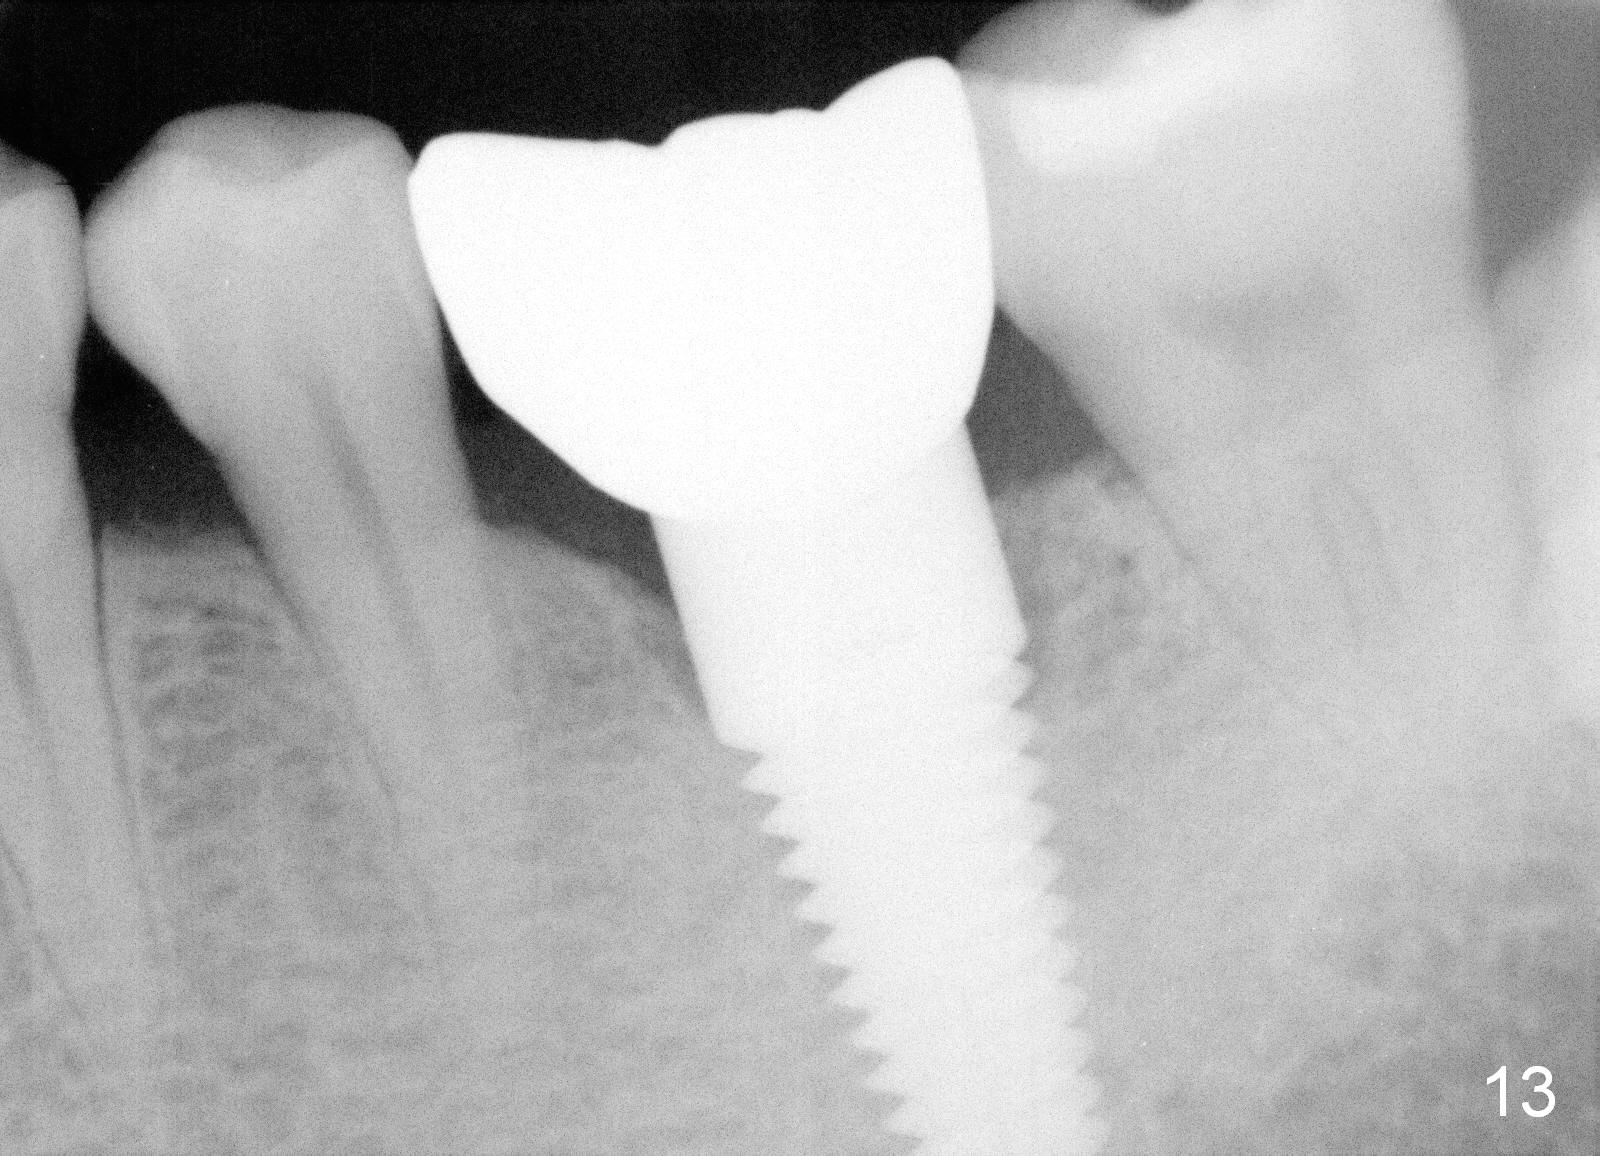

There is a thick gingival band buccal to the implant 7 months postop (Fig.9 *). Osteointegration occurs (Fig.10). The most unexpected finding is the formation of the papillae (Fig.11 *) when the permanent crown is seated. The cosmetic result is due to immediate placement of the large implant. Delayed implant usually cannot achieve this type of outcome.

Two and a half months post cementation, the buccal metal show is much less and confined to the midbuccal portion. It appears that the papillae increase their mesiodistal dimension (data not shown). Bone appears to remain stable over the implant surface 2.5 and 9 months post cementation (Fig.12 >,13). The papillae around the implant crown remain normal 11 months post cementation (Fig.14 *). No bone loss is noticed 26 (Fig.15) or 38 (Fig.16) months post cementation. There is no bone loss around the 7x17 mm tissue-level implant 6 years 8 months post cementation (Fig.17).